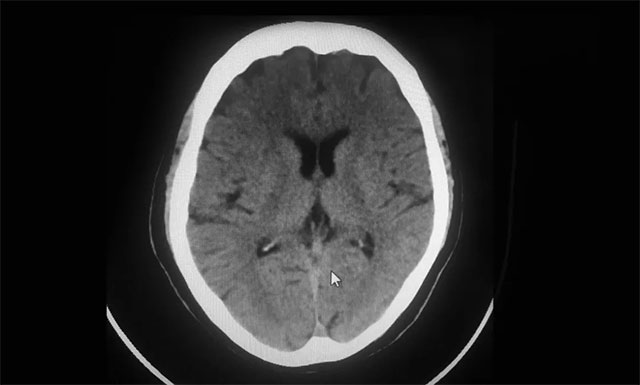

▲ 影像科平扫CT:排除脑出血

从急诊科14:37接诊,患者14:43建立静脉通道,到14:56影像科平扫CT排除脑出血,并告知家属征得同意,再到15:17接受溶栓,急诊科、脑血管病科、影像科、检验科等多个科室通力合作,发挥多学科联动优势,无缝对接,DNT用时为40分钟,为抢救患者的大脑功能赢得了宝贵时间。